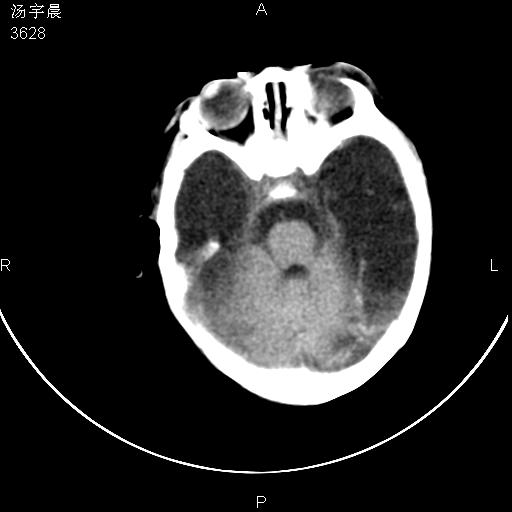

早产儿,现两月大,2月份在某医院诊断病毒性脑炎并治疗,mri报右颞部脑白质片状长t2信号,脑白质模糊。其他不详,现家属要求ct复查 。

双侧大脑半球大片状低密度,无明显占位表现, 符合病毒性脑炎。

小儿病毒性脑炎ct表现缺乏特异性,但其定位分布有一定特异性,单纯疱疹病毒性脑炎ct表现以颢叶病变为主,同时可累及其他脑区或伴出血,乙型脑炎表现为基底及丘脑的病变,流行性腮腺病毒性脑炎则ct表现可正常,故ct检查对病毒性脑炎的定性有重要的价值。 本例支持:病毒性脑炎的后遗改变!